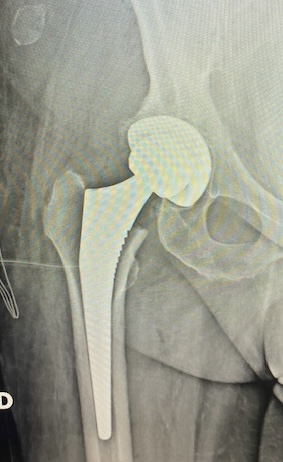

PRÓTESIS DE CADERA Y RODILLA:

Cuando el daño articular es tan importante (artrosis) que ya no responde a tratamiento conservador, está indicado realizar un reemplazo articular con IMPLANTES que recuperen la función articular y eliminen el dolor. Se trata de tratamientos DEFINITIVOS.

Estas cirugías precisan ingreso hospitalario de unos 5 días y la recuperación va desde 6 semanas hasta 3-4 meses.

Prótesis total de cadera